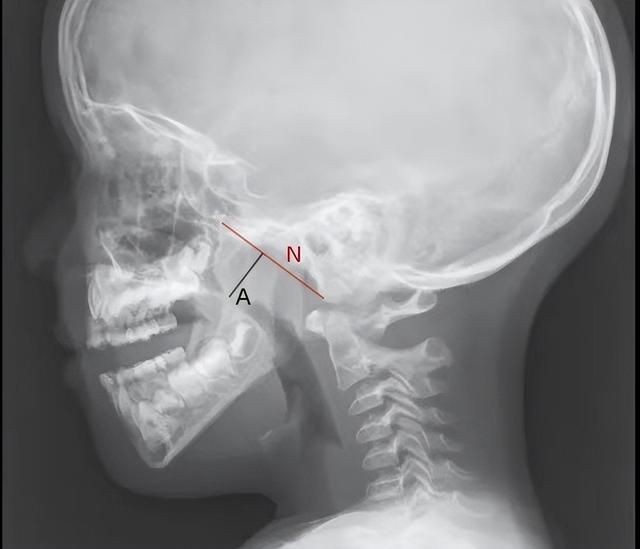

A/N>0.,腺样体肥大,鼻咽部气道狭窄